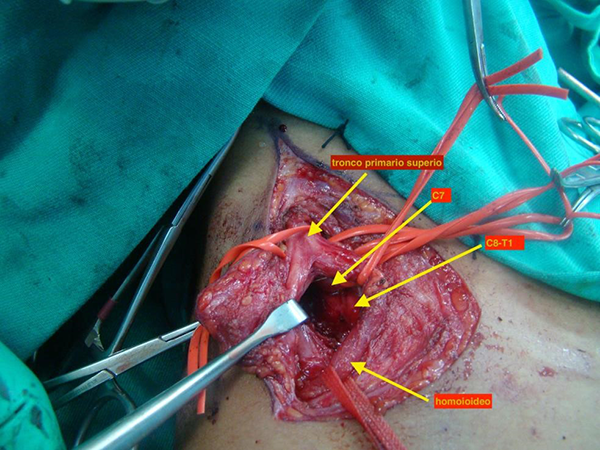

Se realiza abordaje del plexo braquial supra clavicular (foto 3) en el que se identifica tumoración ósea que comprime las raíces inferiores del plexo braquial a nivel supraclavicular.

Foto 3. Abordaje del plexo braquial a nivel supraclavicular. Identificación del tronco primario superior y sus divisiones.

Se realiza radioscopia para identificar trayecto de difícil interpretación por el tipo de tejido cartilaginoso (foto 4) y resección ósea y neurolisis de las raíces del plexo braquial (foto 5).

Foto 5. Exostosis cervical que comprime las raíces inferiores C8 y T1

Foto 6. Tras exéresis de exostosis cervical, neurólisis de las raíces de plexo